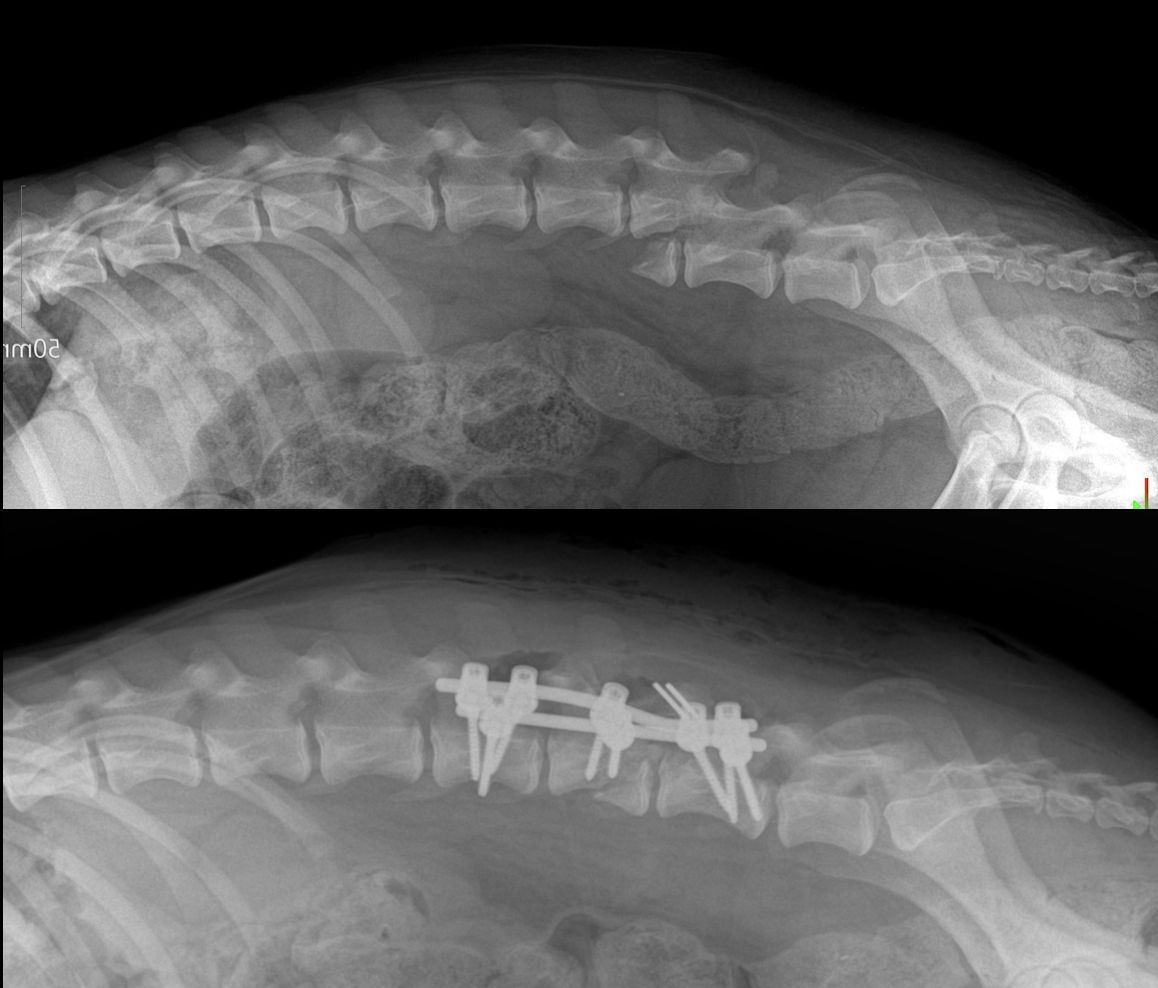

Am 25., am Weihnachtstag, waren wir auf dem Weg nach Tutrakan. Kurz nach dem Ort Volovo bemerkten wir Merry, wie sie im Schlamm und Blut am Straßenrand lag. Wir nahmen sie sofort mit und brachten sie in die Tierklinik „Zdravets“ in Ruse, wo ihr Erste Hilfe geleistet wurde und sie stationär stabilisiert wurde.

Glücklicherweise überlebte Merry die Nacht, jedoch zeigte das Röntgenbild eine schwere Verletzung der Wirbelsäule. Wir nahmen Kontakt mit Dr. Hristov von der Klinik Elpida in Varna für eine Konsultation auf und brachten Mary am 28. nach Varna zur Untersuchung. Am 29. fand die Operation statt, die sehr gut verlaufen ist.

Nach den heutigen Informationen frisst Merry gut und ist sehr fröhlich. Sie hat sogar schon einige kleine „Unfug“-Momente gehabt, da sie am liebsten schon wieder laufen und rennen möchte. Leider hat sich ihr neurologischer Zustand bisher nicht verändert – sie kann ihre Hinterbeine weiterhin nicht bewegen.